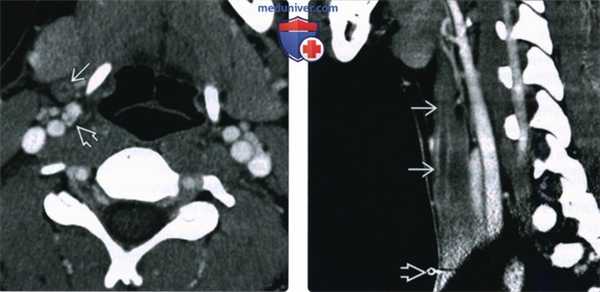

(Слева) При аксиальной МРТ Т1ВИ С+ FS визуализируется небольшая многокамерная киста, накапливающая контраст по типу «ободка», расположенная спереди от сонной артерии, находящейся в открытом состоянии, и снаружи от вершины левого грушевидного синуса.

(Справа) При корональной КТ с КУ визуализируется объемное образование воспалительного характера, смещающее левую долю щитовидной железы книзу. Ткани, окружающие свищевой ход, начинающийся на уровне вершины грушевидного синуса, воспалены.

(Слева) При аксиальной КТ с КУ в левой половине шеи визуализируется многокамерное скопление жидкости с включениями газа, накапливающее контраст. Определяются диффузные воспалительные изменения глубоких жировых пластинок и подкожной жировой клетчатки, границы которых становятся смазанными. Левая грудино-ключично-сосцевидная мышца увеличена в размерах, что позволяет сделать вывод о миозите.

(Справа) На рентгенограмме в прямой проекции, выполненной этому же пациенту в момент проглатывания бариевой взвеси, визуализируется свищевой ход, заполненный бариевым контрастом, начинающийся от вершины левого грушевидного синуса и спускающийся в мягкие ткани нижних отделов шеи слева.